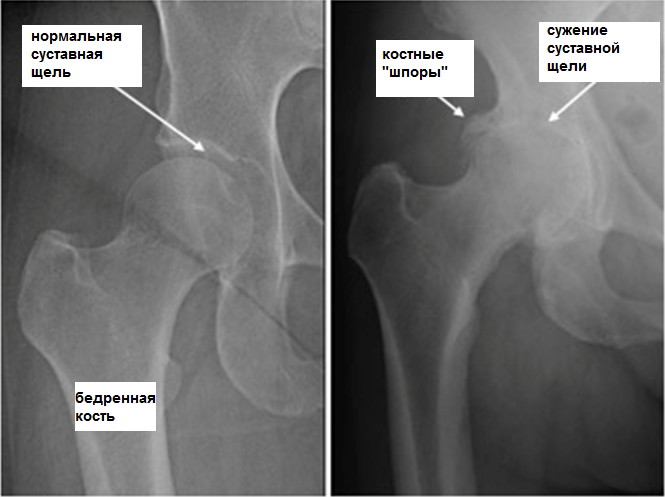

При II степени артроза тазобедренного сустава боли появляются и в состоянии покоя, в том числе ночью. После физической нагрузки пациент начинает прихрамывать, формируется характерная «утиная» походка. Появляются так называемые стартовые боли – после продолжительного периода неподвижности первые несколько шагов вызывают боль и дискомфорт, которые затем проходят, а потом возвращаются после длительной нагрузки. В пораженном суставе ограничивается объем движений (отведение, внутренняя ротация). На рентгенограмме видно, что суставная щель неравномерно сужена и ее просвет составляет 50% от нормы. Остеофиты располагаются как по внутреннему, так и по внешнему краю суставной впадины, выходя за границы хрящевой губы. Контуры головки бедренной кости становятся неровными за счет деформации.

При III степени артроза тазобедренного сустава боли интенсивные и постоянные, не прекращающиеся ночью. Ходьба значительно затруднена, пациент вынужден опираться на трость. Объем движений в пораженном суставе резко ограничивается, позже полностью прекращается. Из-за атрофии мышц бедра таз отклоняется во фронтальной плоскости и происходит укорочение конечности. Пытаясь компенсировать это укорочение, пациенты при ходьбе вынуждены отклонять туловище в сторону поражения, что еще больше увеличивает нагрузку на больной сустав. На рентгенограммах выявляются множественные костные разрастания, значительное сужение суставной щели и выраженное увеличение головки бедренной кости.

Артроз тазобедренного сустава на рентгеновском снимкеПри заболеваниях позвоночника в некоторых случаях происходит сдавливание нервных корешков спинного мозга с развитием болевого синдрома. Боли могут иррадиировать в область тазобедренного сустава и имитировать клиническую картину его поражения. Однако характер боли при корешковом синдроме несколько иной, чем при артрозе тазобедренного сустава: